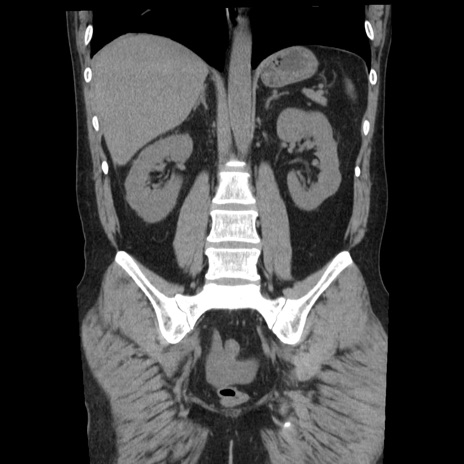

症例29(冠状断像)

【症例】40歳代男性

【現病歴】2日前から胃痛あり。徐々に周期的な激痛に変化した。本日になっても激痛があるため受診。

【身体所見】意識清明、BT 38-39℃台あり、腹部:膨満、やや硬、右下腹部に圧痛あり。

【データ】WBC 8500、CRP 23.26